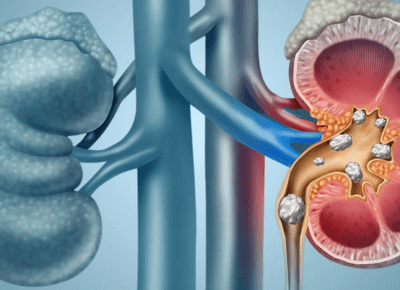

Dialysis is a medical procedure that performs the essential functions of the kidneys when they are no longer able to do so effectively. The kidneys filter waste, excess fluids, and toxins from the blood, maintaining a healthy balance of electrolytes and fluids. When kidney function declines due to conditions such as chronic kidney disease (CKD) or acute kidney injury, dialysis helps by mechanically filtering the blood.

There are two primary types of dialysis: hemodialysis and peritoneal dialysis. Hemodialysis involves using a machine to filter blood outside the body, while peritoneal dialysis uses the lining of the abdomen to filter blood internally.

For patients with severe kidney damage or failure, dialysis becomes a life-saving treatment. It helps prevent the buildup of dangerous waste products and excess fluids, reducing complications like swelling, high blood pressure, and heart issues. Without dialysis or a kidney transplant, survival becomes difficult for patients with end-stage renal disease.